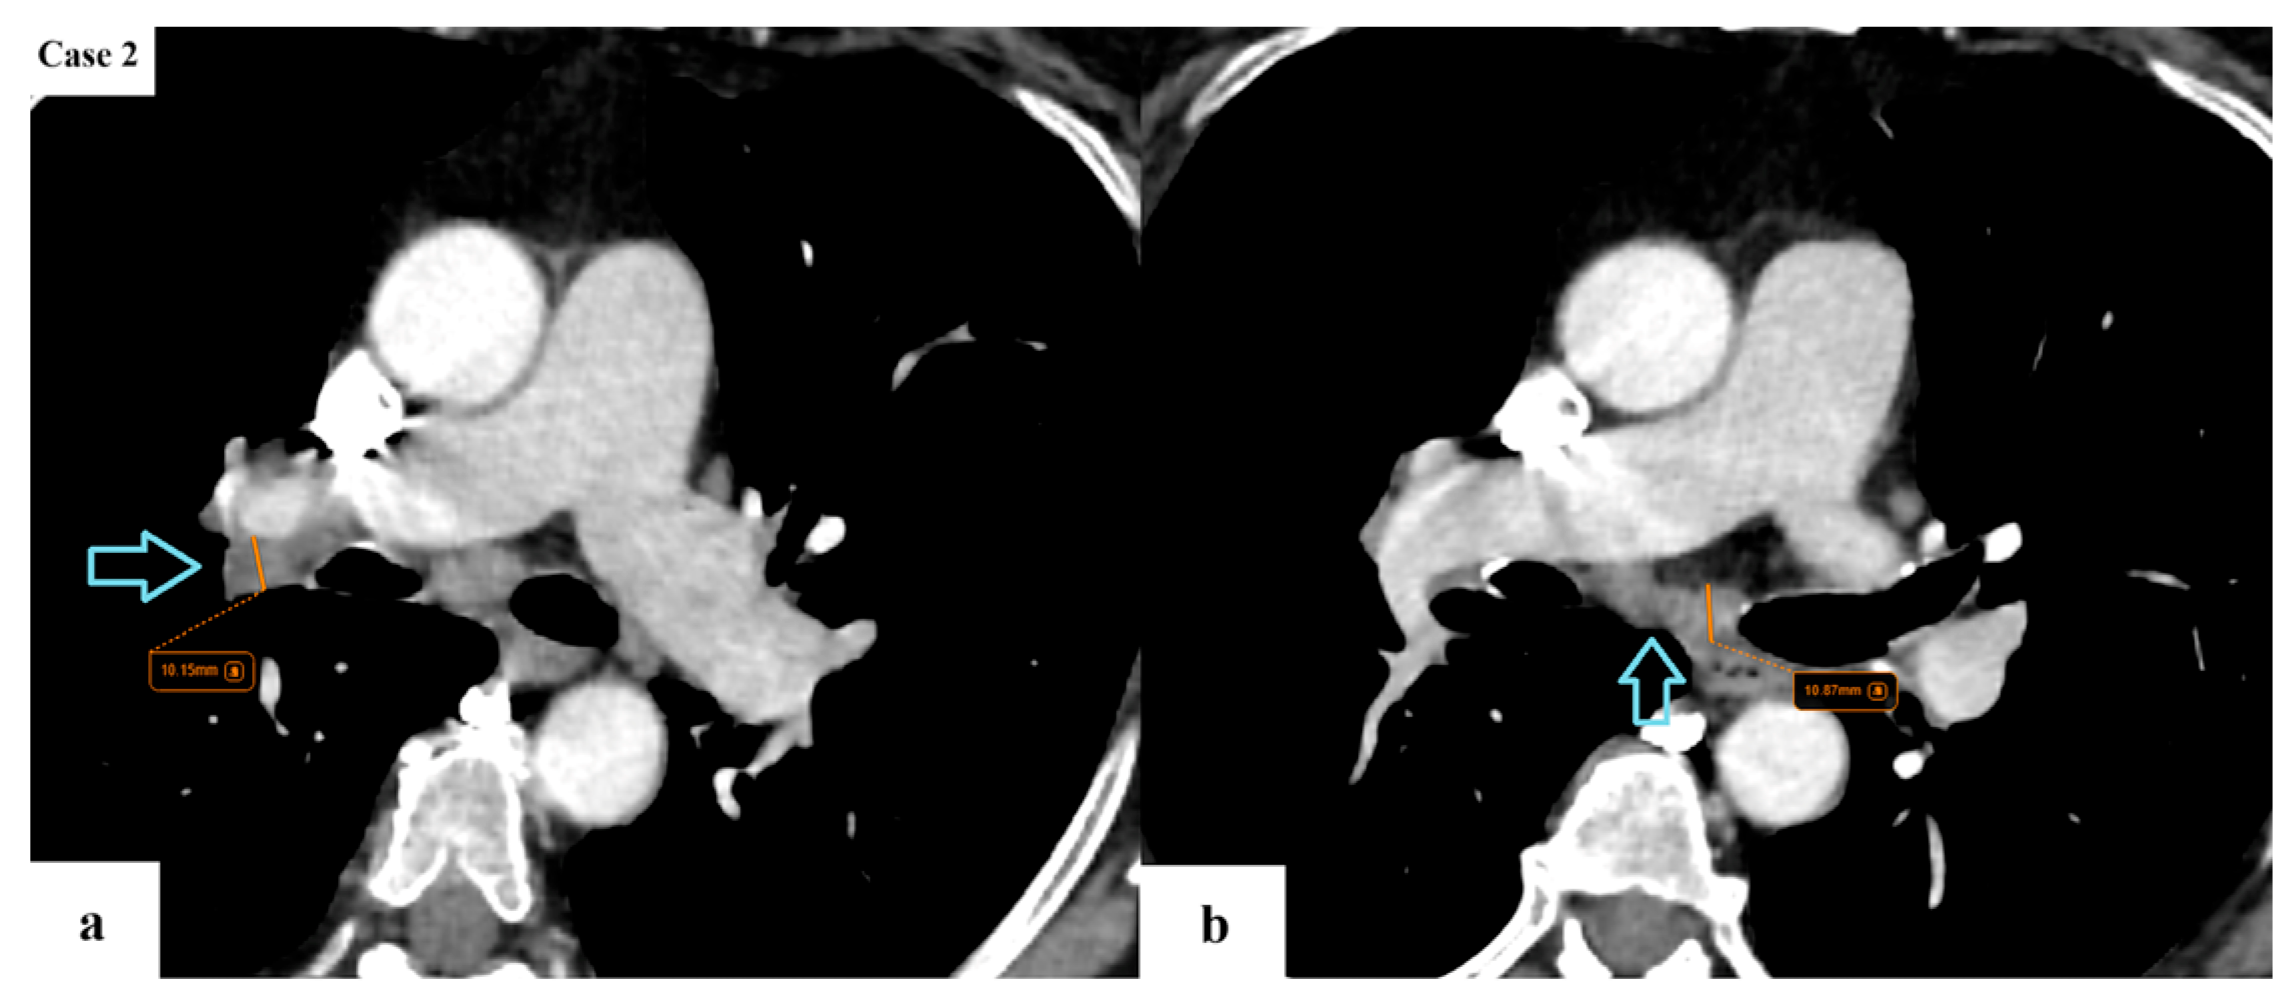

- Argentieri, G.; Valsecchi, C.; Petrella, F.; Jungblut, L.; Frauenfelder, T.; Del Grande, F.; Rizzo, S. Implementation of the 9th TNM for Lung Cancer: Practical Insights for Radiologists. Eur. Radiol. 2025, 35, 4395–4402. [Google Scholar] [CrossRef] [PubMed]

- Erasmus, L.T.; Strange, C.D.; Ahuja, J.; Agrawal, R.; Shroff, G.S.; Marom, E.M.; Truong, M.T. Imaging of Lung Cancer Staging: TNM 9 Updates. Semin. Ultrasound CT MRI 2024, 45, 410–419. [Google Scholar] [CrossRef]